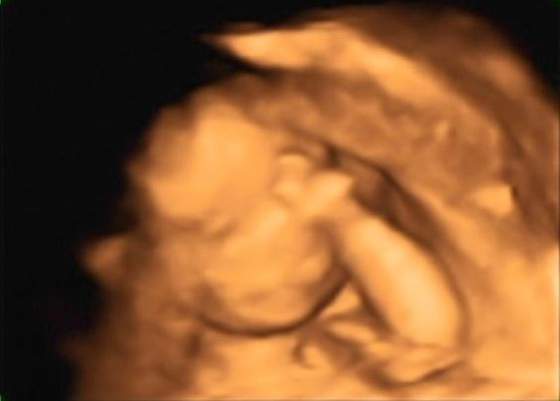

U mnie jest różnica, bo za normalne USG, które mam na wizycie w gina płacę 100złŚliczne dzieciaczki Sivle i Baśka ... wielkie gratki :-)

Zgadzam sie z Wami ,ze takie badanie prenatalne w trybie 3D/4D to niemały wydatek. U mnie kosztuje to 170zł, ale normalna wizyta kosztuje 100zł , więc czy az taka różnica?!